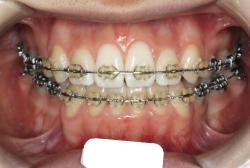

上下顎前突

上下とも歯列が前方に突出していて口を閉じにくい、または口を閉じたときに口元が前に出ている状態を上下顎前突といいます。

歯並びがきれいでも前歯が前に傾いていて、口元に突出感があることもあります。前歯が外に傾くと唇が押し出されることになりますので、少し不満げな口元になってしまいます。

「上の前歯の凸凹」という主訴で来院したケースです。確かに上の左右二番目の歯が内側に引っ込んでいて、凸凹が目立つ状態です。歯並びの凸凹を矯正学では 叢生(そうせい)と言いまして、確かにご本人的にはそこが気になるのですが、矯正学的には前歯の前突の方がより問題となるケースです。

初診時の写真をご覧いただくと、何となく前歯が前傾しているのが感じられると思うのですが、よく見ると上の歯だけでなく、下の前歯も前傾しているのがわかります。このように上の前歯も下の前歯も両方外向きになっている症状のことを、「上下顎前突」と言います。こういうケースの場合は上下左右の小臼歯を抜く(つまり4本抜歯する)ことで配列の中に隙間を作り、その隙間を利用して配列を揃えるだけでなく、 前歯を内側に入れていく治療をします。

治療前後の口元の変化です。前歯の角度が大きく変わりました。治療前は外向きの前歯に押されて、口元がふくらみすぎの状態でした。黄色の線は鼻の頂上と顎の先端を結んだ線で、審美線と言います。審美線と唇はあまり接触しない方が良いと考えられています。矢印の部分がかなりラインオーバーしています。治療後はよりスマートで美しい横顔になりました。このように歯並びを直すと、唇の表情ひいてはお顔全体の表情にも良い変化が生まれます。